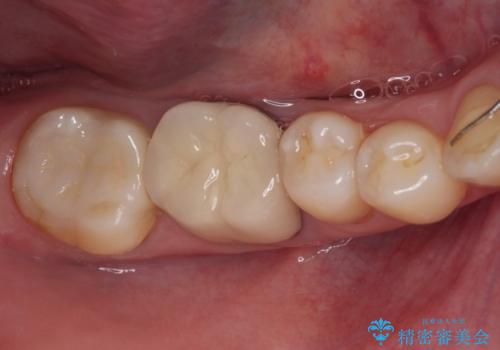

捻れた前歯と銀歯のブリッジを治したい ワイヤー矯正とオールセラミックブリッジ